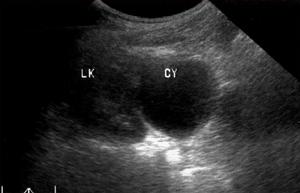

1.體格檢查,B超或CT發現腎囊腫。

2.尿路造影術顯示患腎有占位性病變,但CT或MRI除外囊腫惡變或腎癌液化。